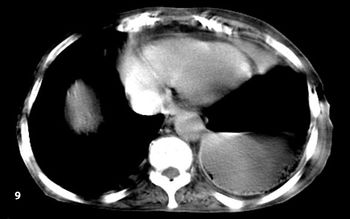

Case History: A 33-year-old patient presented with history abdominal discomfort for 5 months.